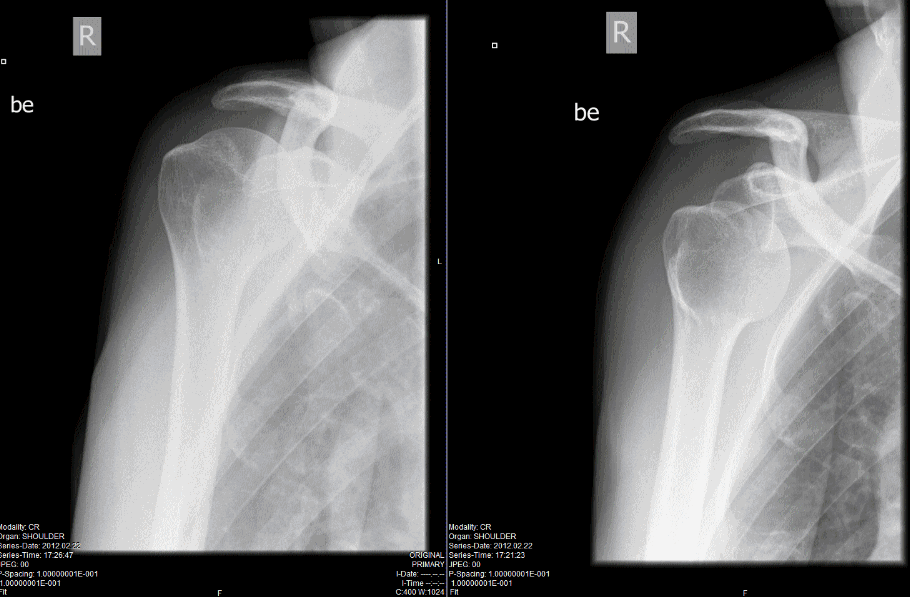

From jetem.org

Bilateral Shoulder Dislocation after Ski Injury JETem How Long To Ski After Dislocated Shoulder A dislocated shoulder is a common and painful injury that many people, of all ages,. At your appointment, your doctor. It may take up to 16 weeks to fully return to playing some. Aim to do all these shoulder. in a shoulder dislocation, the head of the upper arm bone (humerus) may come either partially or completely out of. How Long To Ski After Dislocated Shoulder.